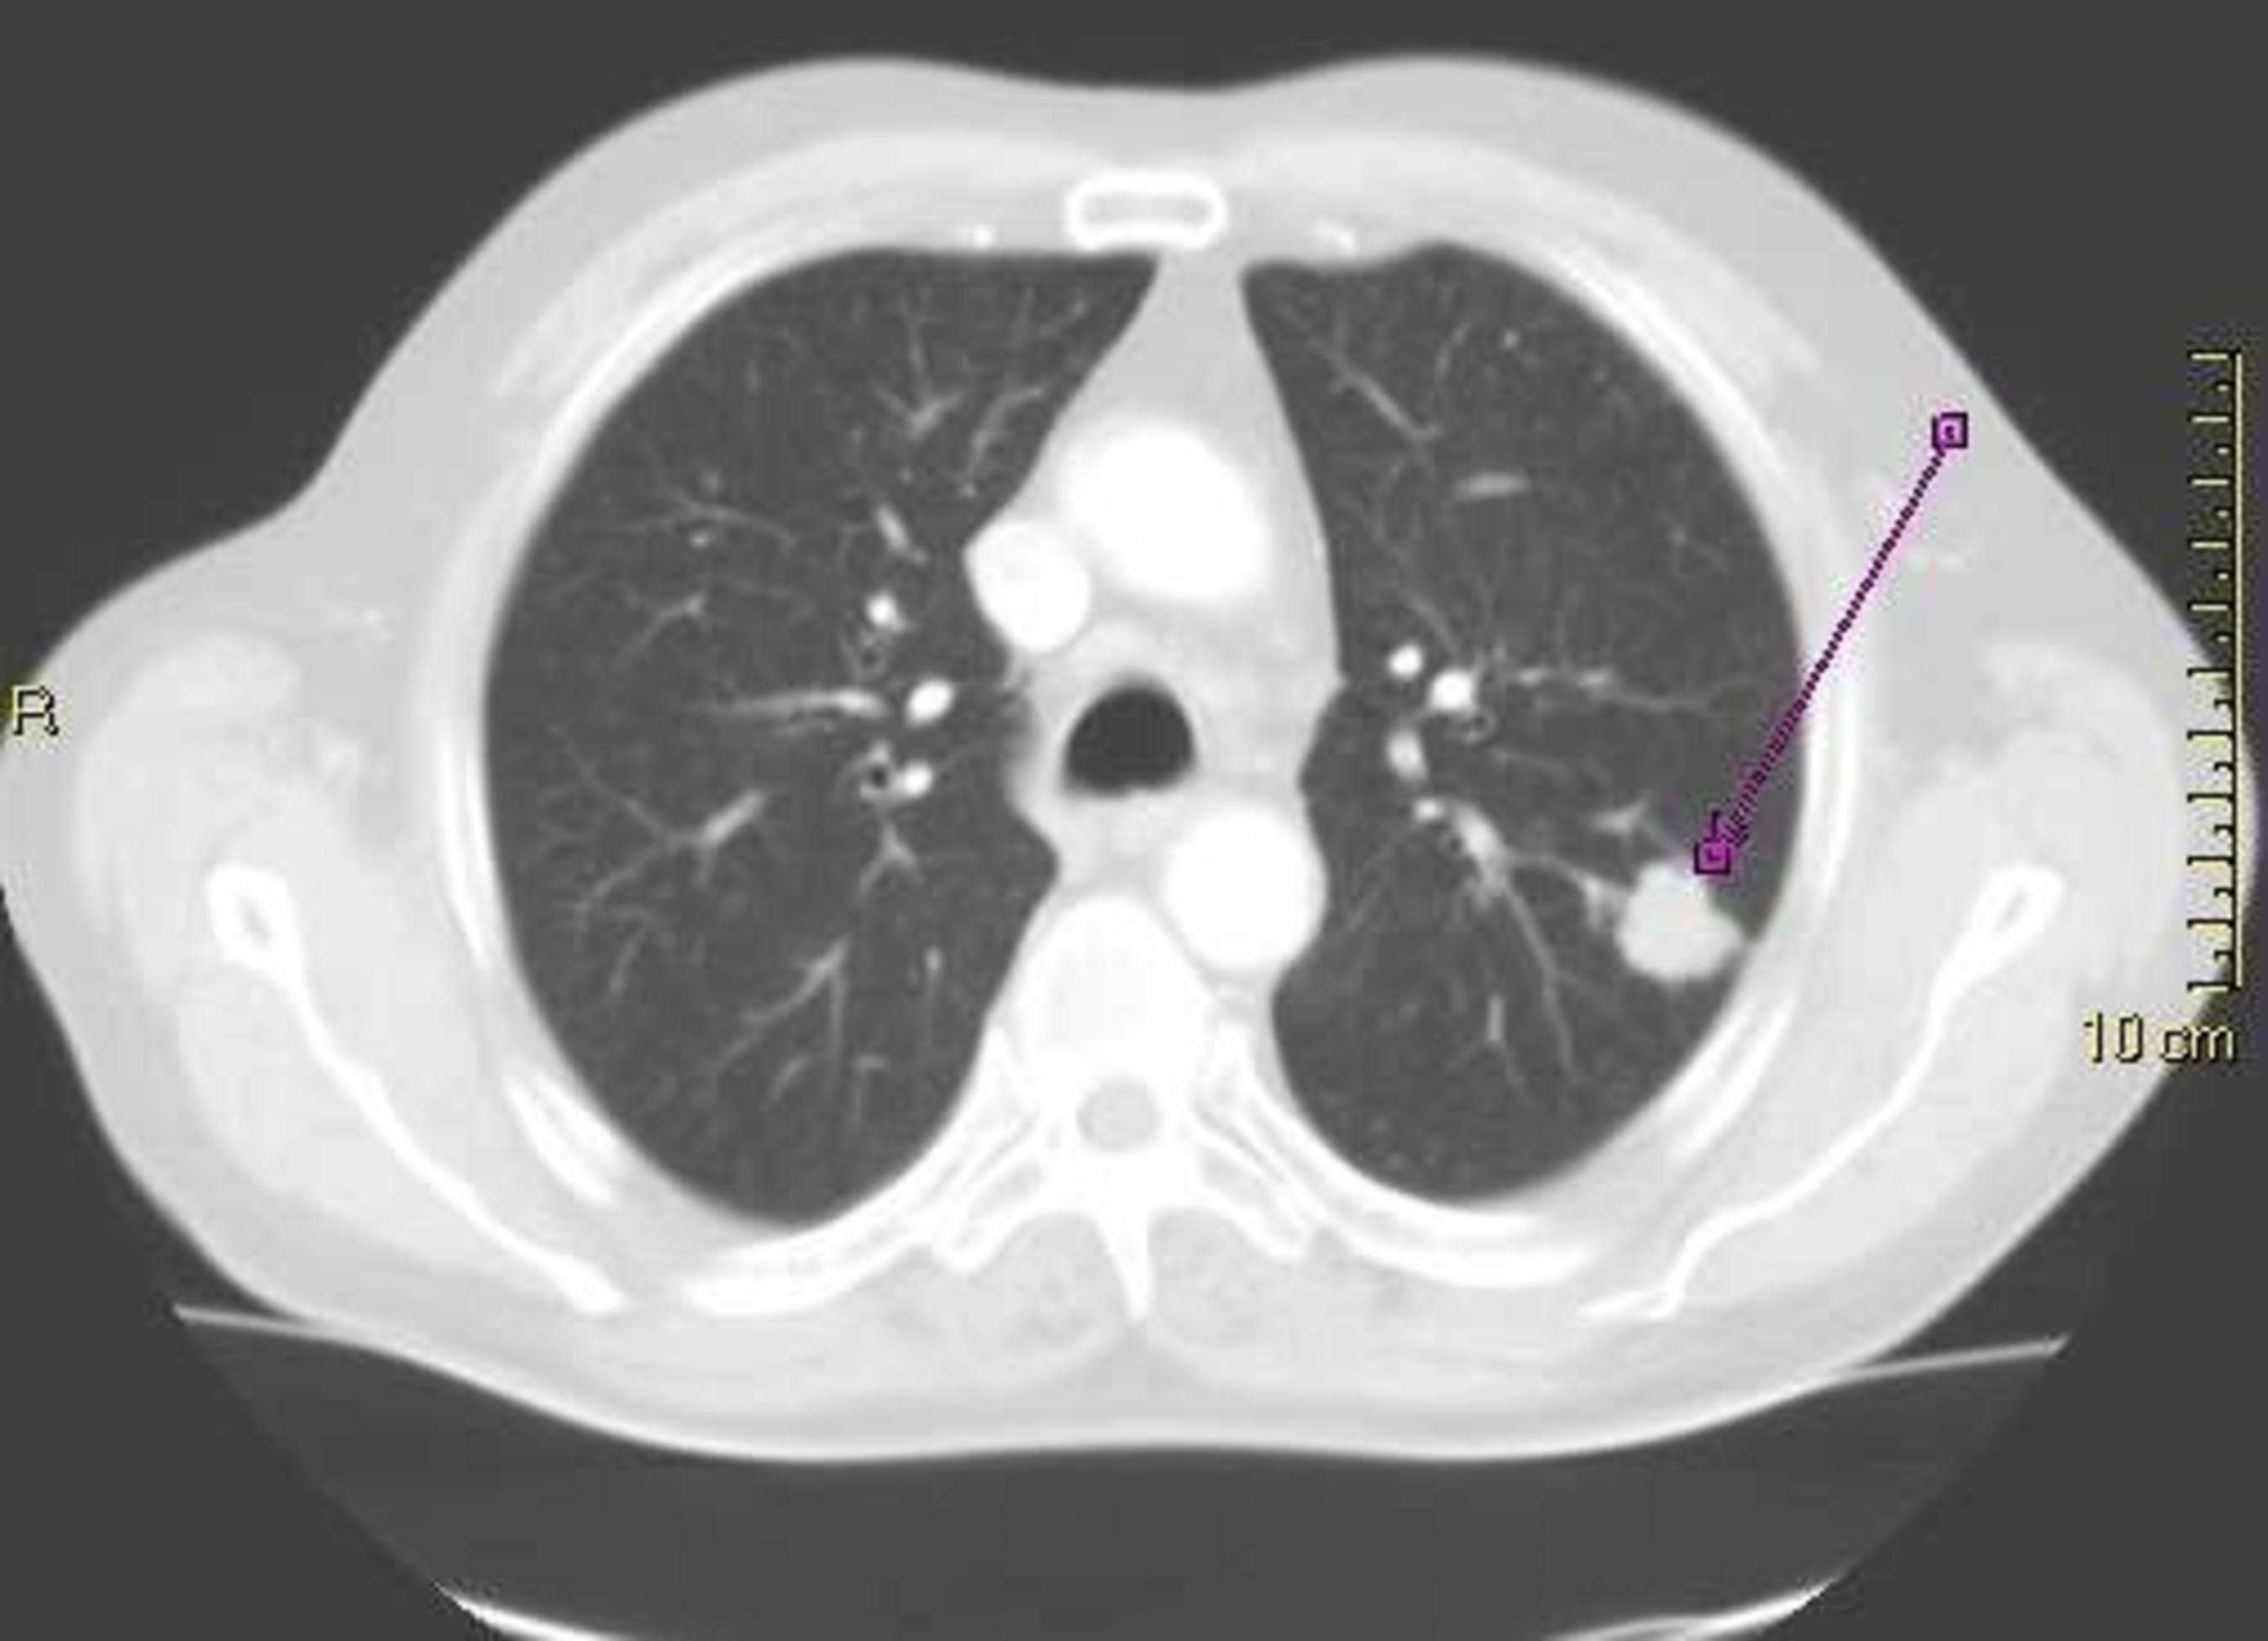

DENVER, Oct. 10, 2016 /PRNewswire/ -- A major academic center has chosen LungDirect (Eon) over several competitors to manage their pulmonary nodule patients. LungDirect, the only software system designed to manage incidentally found nodules, will be utilized to evaluate the most effective treatment algorithm for patients with incidentally found nodules. LungDirect will automate methods for identification, notification, and registration into the LungDirect dashboard, and is expected to register 5,000 patients over 20 months. Currently, lung cancer is the leading cause of all cancer death, claiming more lives each year than breast, prostate, and colon cancer combined. Often times a pulmonary nodule, referred to as a spot on the lung, is identified on a CT scan for an order unrelated to the lungs. LungDirect alerts providers, both internally and externally, when a nodule patient is detected, and works to ensure patients receive the appropriate follow-up care.